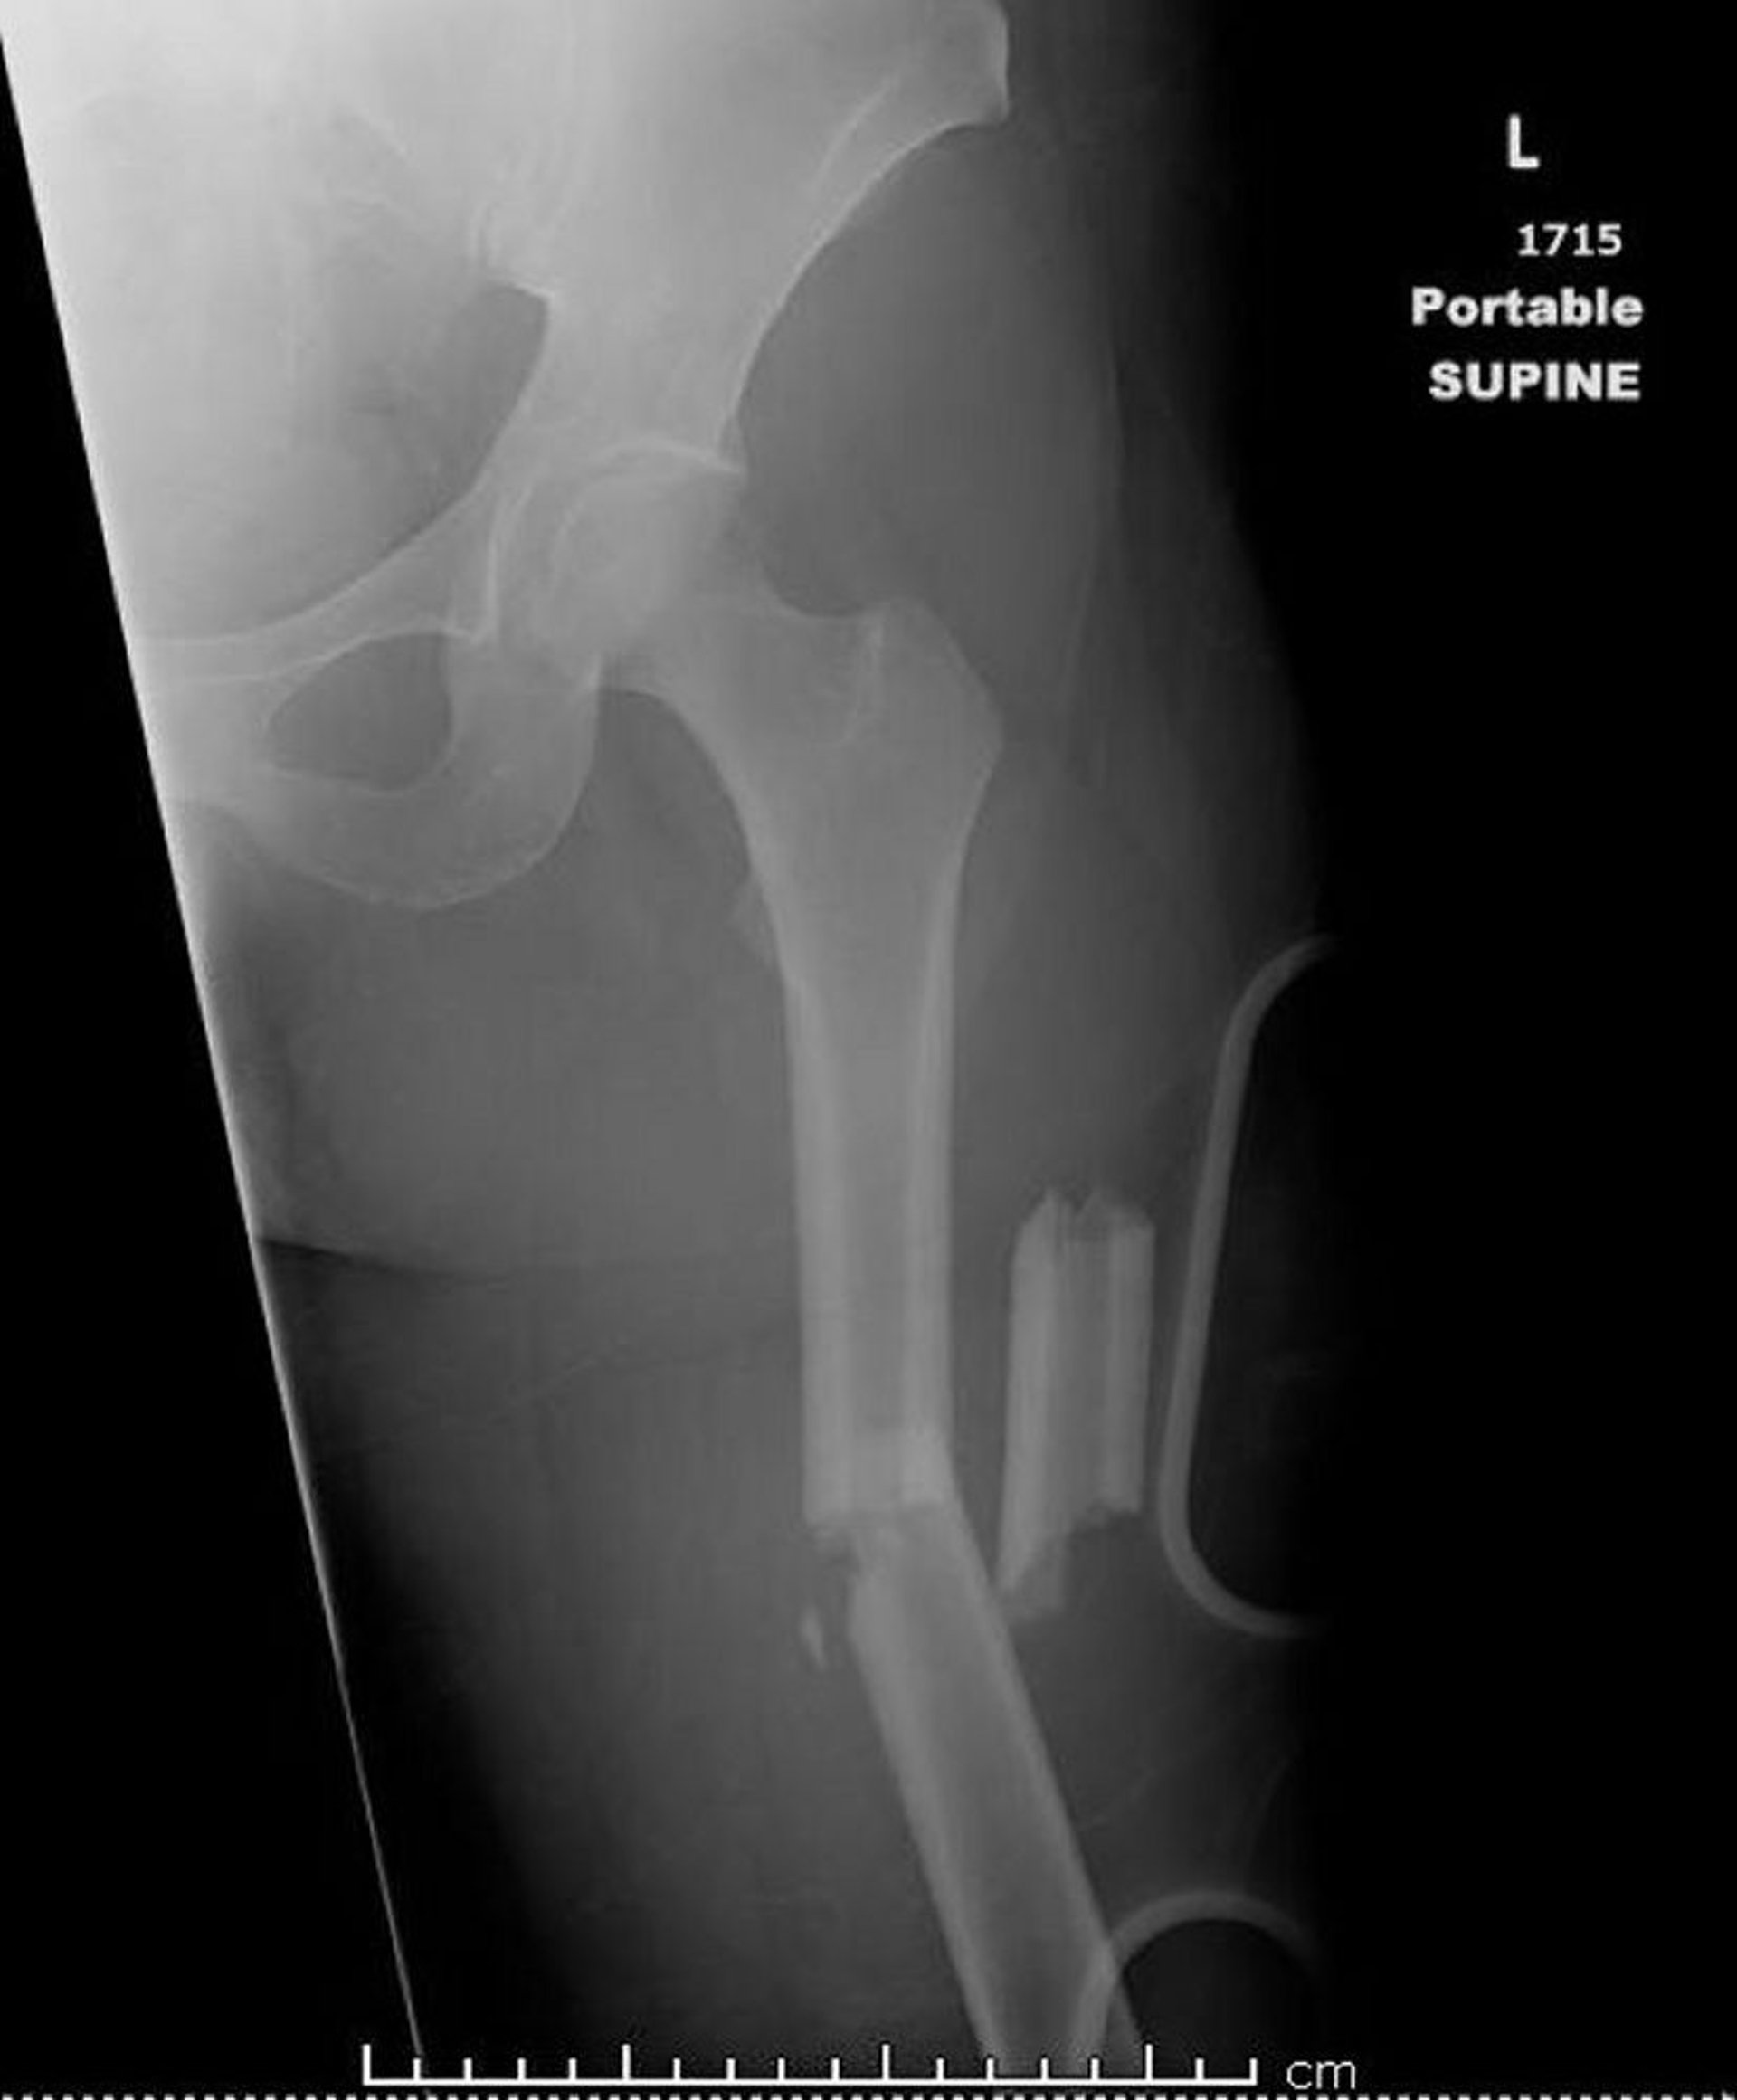

골간부 허벅지뼈 골절

이 영상은 두 곳 이상에서 골절된(분쇄된) 대퇴골을 보여줍니다.

영상 제공: Danielle Campagne, MD.